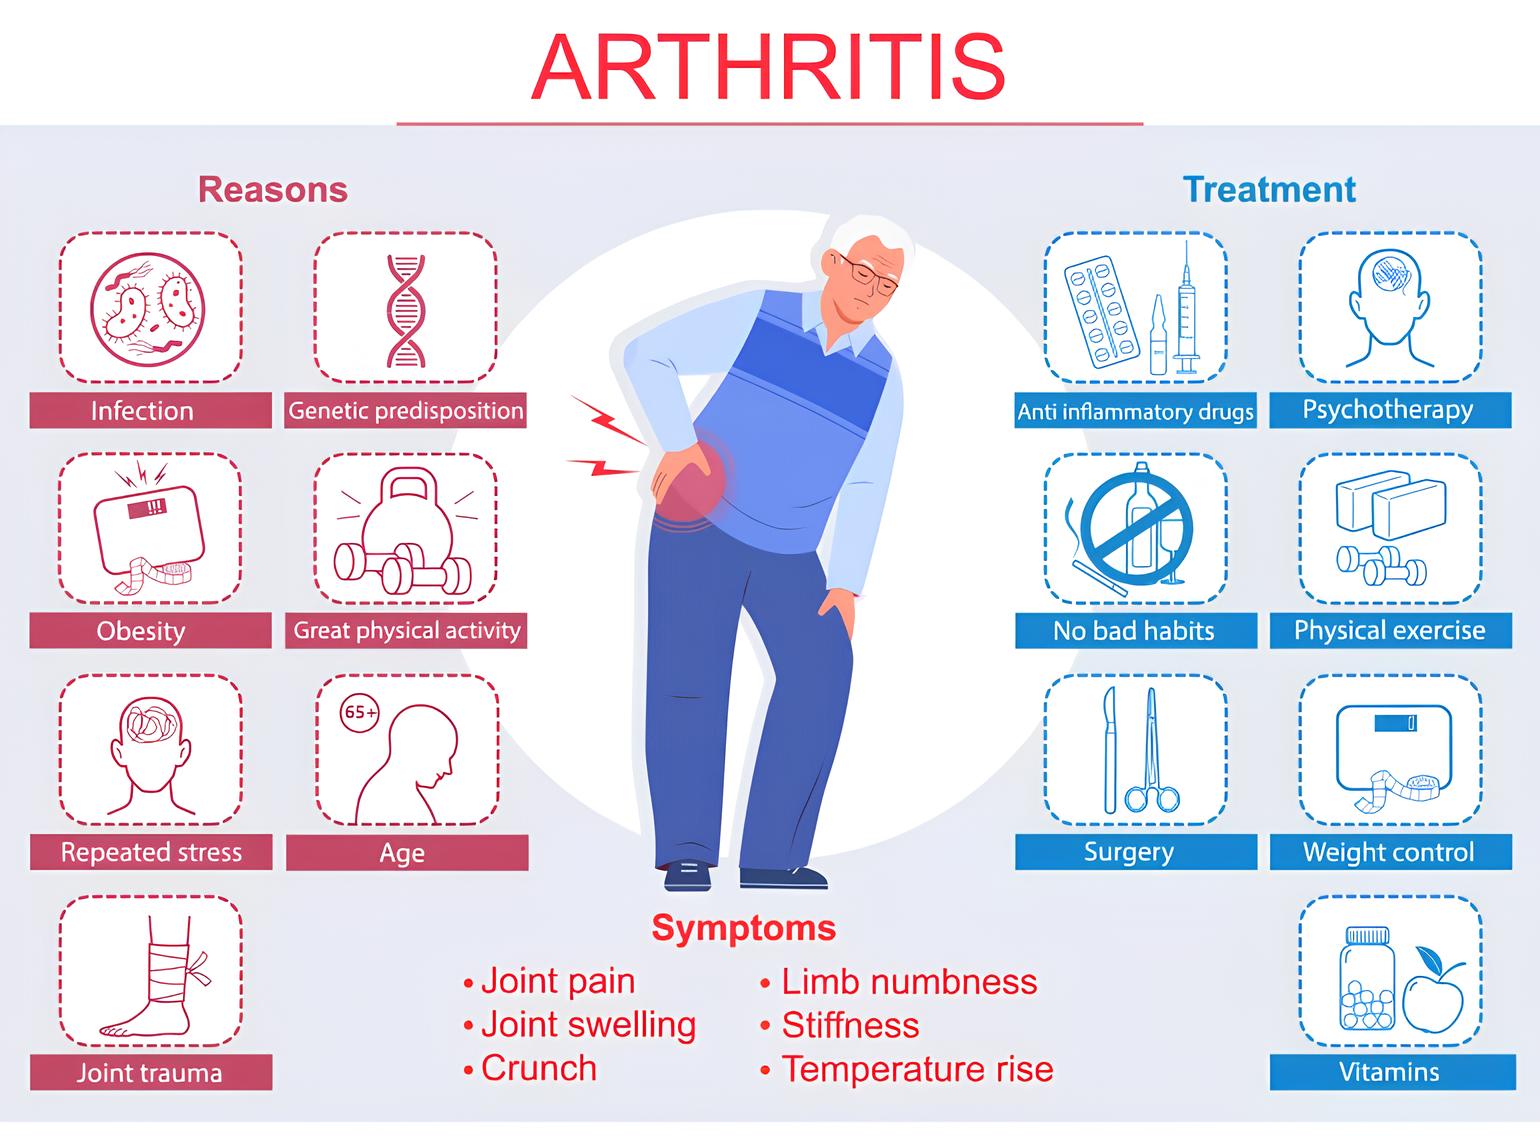

آرتریت یک اصطلاح کلی برای بیماری های التهابی مفصل است و بیش از صد نوع مختلف را در بر می گیرد. این گروه از بیماری ها می توانند علل متفاوتی مانند اختلالات خودایمنی، عفونت ها یا مشکلات متابولیک داشته باشند و معمولاً با علائمی مثل درد، تورم، گرمی، قرمزی مفصل و خشکی طولانی مدت صبحگاهی همراه هستند. آرتریت میتواند چندین مفصل را به طور همزمان درگیر کند و در هر سنی دیده شود.

روماتیسم مفصلی، نقرس، آرتریت عفونی و آرتریت پسوریاتیک از شایع ترین انواع آرتریت هستند. در بسیاری از این بیماری ها، التهاب نقش اصلی را در تخریب مفصل دارد و در صورت عدم درمان مناسب، ممکن است باعث آسیب دائمی به مفاصل و کاهش عملکرد حرکتی فرد شود.

علائم آرتریت

آرتریت شامل التهاب حاد و مزمن مفاصل است که اغلب با درد و آسیب ساختاری مفصل همراه است. علائم آرتریت معمولا شامل موارد زیر هست.

درد مفاصل

- درد معمولاً در ناحیه مفاصل حس میشود، و ممکن است در مفاصل مختلف مانند زانو، شانه، انگشتان، یا مچ دست وجود داشته باشد.

- ناراحتی و درد میتواند تیز، مبهم، سوزشی، یا ضربان دار باشد و شدت آن از ملایم تا شدید متغیر است.

- درد ممکن است به طور پیوسته یا متناوب باشد و در برخی مواقع به ویژه در صبح ها یا بعد از استراحت طولانی تر احساس شود.

تورم و قرمزی مفاصل

- مفصل ممکن است متورم و برجسته به نظر برسد. تورم به دلیل تجمع مایع در مفصل یا التهاب بافت های اطراف است.

- پوست اطراف مفصل ممکن است قرمز و گرم به لمس باشد، که نشان دهنده التهاب و گاهی عفونت است.

محدودیت حرکت مفاصل

- درد، تورم و تخریب مفصل میتواند باعث کاهش دامنه حرکت مفصل شده و انجام فعالیتهای طبیعی را دشوار کند.

- احساس سفتی در مفصل، به ویژه در صبح ها یا بعد از نشستن طولانی مدت، شایع است. این سفتی میتواند حرکت مفصل را محدود کند.

احساس خستگی و ضعف

- بسیاری از انواع آرتریت به دلیل التهاب مزمن، ممکن است به خستگی و احساس کسالت عمومی منجر شوند.

- التهاب مزمن و درد می تواند به ضعف و کاهش قدرت جسمانی منجر شود.

علائم عمومی آرتریت

- در مواردی که آرتریت به دلیل عفونت یا التهاب شدید باشد، ممکن است تب و لرز وجود داشته باشد.

- برخی بیماران ممکن است دچار کاهش وزن غیر مستقیم به دلیل درد و اختلالات مربوط به اشتها شوند.

درمان آرتریت

درمان آرتریت شامل رویکرد های مختلفی برای کاهش درد، بهبود عملکرد مفصل و بهبود کیفیت زندگی بیماران است. گزینه های درمانی معمولا شامل دارو ها، فیزیوتراپی، اصلاح سبک زندگی و در برخی موارد مداخلات جراحی است.

دارو ها اغلب شامل دارو های ضد التهابی غیر استروئیدی (NSAIDs)، کورتیکواستروئید ها و دارو های ضد روماتیسمی اصلاح کننده بیماری (DMARDs) برای اشکال التهابی آرتریت، مانند آرتریت روماتوئید است. این دارو ها به کاهش درد و التهاب کمک می کنند و با کنترل علائم آرتریت، بیماران را قادر می سازند تا سبک زندگی فعال تری داشته باشند.